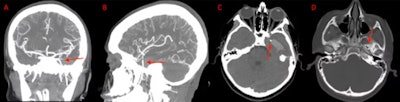

(A) and (B) Coronal and sagittal view of the CT angiogram shows the wire penetrating through the skull floor of a 12-year-old boy. (C) Axial view of CT demonstrates the wire in the temporal lobe and the associated intraparenchymal hemorrhage. (D) Axial bone window CT shows the wire entering through the foramen ovale. Images courtesy of Morgan et al. Licensed by CC BY 4.0.

Imaging aided in the diagnosis of a 12-year-old boy in Texas who experienced a seizure after an orthodontic wire from his braces migrated into his temporal lobe.

After computed tomography (CT) scans and x-rays confirmed the metallic foreign object, which had traveled via the foramen ovale into the temporal lobe, as well as an associated intraparenchymal hemorrhage, the wire was removed without complications. The boy sustained no measurable damage to any structures within or around the foramen ovale, including the carotid artery, which would have been devastating, the authors wrote.